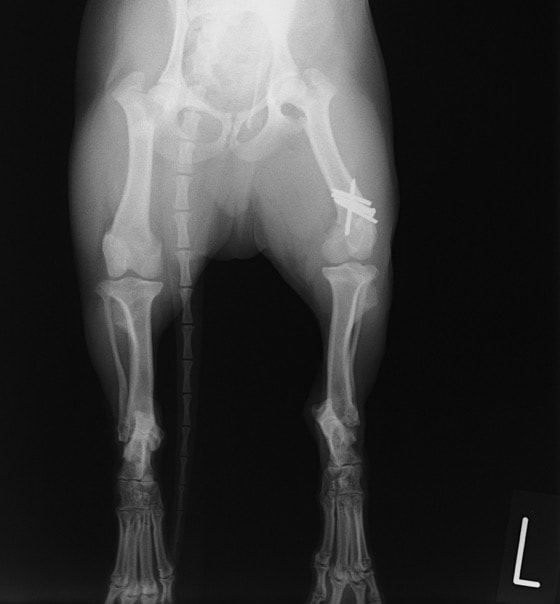

ペルシャ猫 11ヶ月齢 雄

他院にて左大腿骨遠位の成長板骨折(salter-harrisⅠ型)が認められており、治療相談を目的として来院。当院にて、キルシュナーワイヤーを用いたピンニングにより骨折部位の整復を行いました。術後の経過は良好で、現在も経過観察中です。

術後レントゲン

Arthrex社のターゲティングデバイスを用いてピンニングの位置を調整することで、確実な固定を行っています。当院ではこの手術器具以外にも、人の手術にも使用される様々な器具を導入し、手術精度を高め、また医療メーカーと新しい器具の開発、試作にも取り組んでおります。